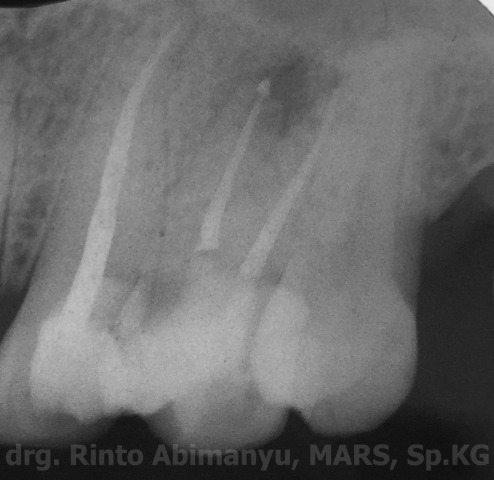

Pada kunjungan ini sudah tidak ada rasa nyeri bila dipakai menggigit, perkusi juga menunjukkan negatif. Pengisian dilakukan dengan tehnik warm vertical condensation menggunakan alat Element Obturation (Sybronendo) dan sealer AH plus (Dentsply).

Foto setelah pengisian..

Setelah pengisian kavitas dibersihkan dari sisa sealer dan guttap

dan ini ronsennya…

Radiografis setelah selesai perawatan